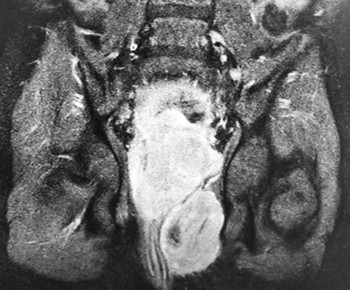

Обследование: ОАК (анемия умеренной степени, СОЭ 21 мм/ч); ОАМ (эритроциты, лейкоциты в большом количестве, белок 0,29, бактерии); БАК: Д-димеры 401 мкг/мл; ликвор (глюкоза 5,8); КТ головного мозга: гиподенсивный участок в левой теменно-затылочной зоне — участок ишемии (?); МРТ ГМ: мультифокальные билатеральные участки гиперинтенсивности в бассейне кровоснабжения сосудов задней циркуляции. (МР-картина может соответствовать синдрому задней обратимой энцефалопатии, васкулиту, эмболическим инфарктам мозга различной степени давности (?)); УЗИ ОБП: гидронефроз с обеих сторон, гиперплазия лимфоузлов; УЗИ мочевого пузыря: весь мочевой пузырь заполнен неоднородными массами, без признаков кровотока, в толще этих масс лоцируется катетер, жидкостной компонент не прослеживается (см. рис. 1); УЗИ БЦА: без патологии; ЭхоКГ: без патологии.

Рисунок 1. Результаты УЗИ мочевого пузыря.